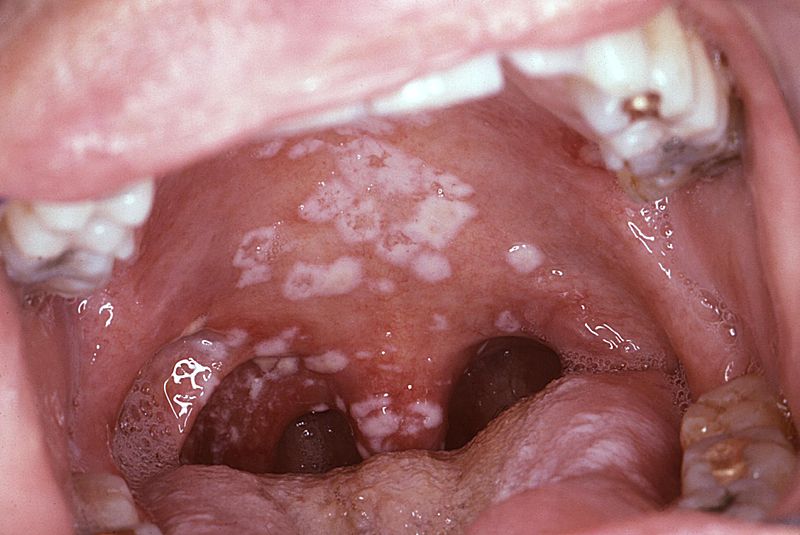

Hairy Leukoplakia

Hairy leukoplakia (HL) is a histological manifestation of HIV infection and is distinguished by parakeratosis of the oral mucosa, hyperkeratosis, keratinization of the epithelium, and numerous intracellular inclusion bodies made up of lipid vacuoles, concentric lamellar structures, and occasionally viral particles within macrophages.

Oral sores are very contagious and frequently lead to the development of systemic diseases.